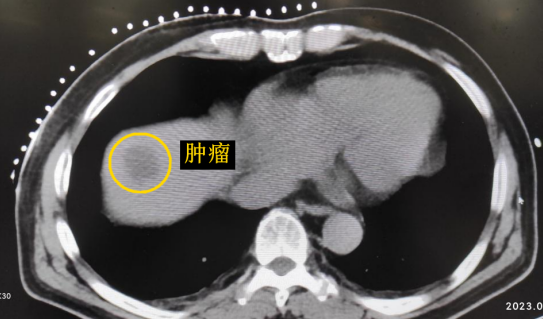

患者老年男性,曾于2021年行結(jié)腸癌手術(shù)。幾月前,發(fā)現(xiàn)肝臟轉(zhuǎn)移瘤,但沒有干預(yù)。近期CT顯示該轉(zhuǎn)移瘤明顯增大,并發(fā)現(xiàn)另一處轉(zhuǎn)移灶。

影像診療科陳寶瑩主任團(tuán)隊(duì)評估后指出,較大的腫瘤位于肝頂部緊貼膈肌,如果繼續(xù)發(fā)展,腫瘤很可能突破肝包膜侵犯到膈肌,建議及時(shí)干預(yù)。病變緊臨膈肌,如果要完全消融,膈肌損傷的可能性就比較大,與其他局部治療方式比較,冷凍消融對周圍臟器、血管及神經(jīng)損傷的可能性較小、安全性更高、患者疼痛感較輕,建議通過CT精準(zhǔn)引導(dǎo)下經(jīng)皮微創(chuàng)冷凍消融治療。

CT精準(zhǔn)定位腫瘤